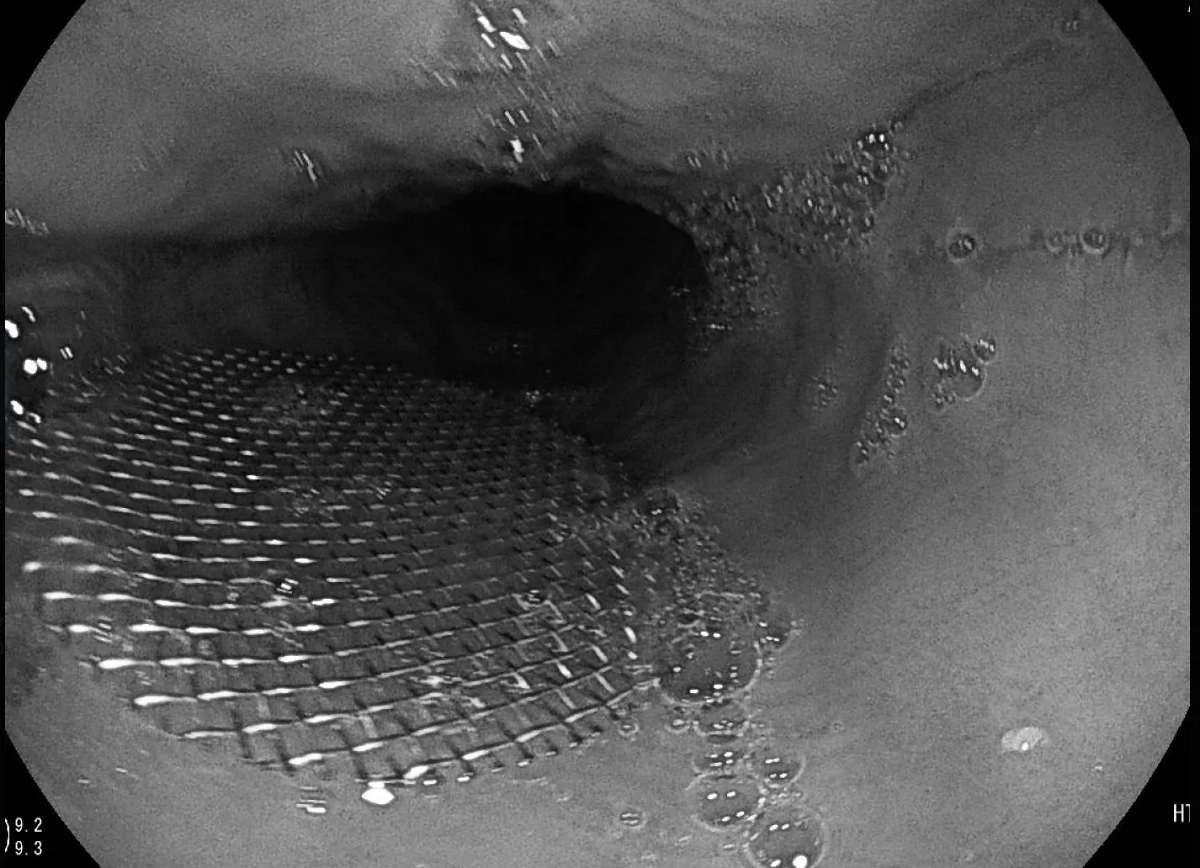

Подмосковные врачи извлекли металлическую сетку из пищевода пациента, который обратился к ним с жалобами на кашель, затруднённое дыхание и ощущение инородного предмета в горле. Как она там оказалась, мужчина, как это часто бывает, объяснить медикам не смог.

Трудность состояла в том, что сетка диаметром почти два сантиметра находилась глубоко и при извлечении могла поранить стенки пищевода, поэтому врачи решили действовать с помощью щипцов для биопсии. Такой инструмент обычно используется для забора биологического материала.

Снимок металлической сетки в пищеводе жителя Подмосковья. Фото предоставлено Лайфу

"Операцию провели под местной анестезией, длилась она полчаса. Наиболее опасным осложнением инородных тел в пищеводе является перфорация — сквозное повреждение, при котором нарушается целостность всех слоёв стенки пищевода. Однако в данном случае благодаря оперативному обращению пациента за медицинской помощью этого удалось избежать", — рассказала Лайфу заведующая клинико-диагностическим отделением Видновской районной больницы Татьяна Шашкова.